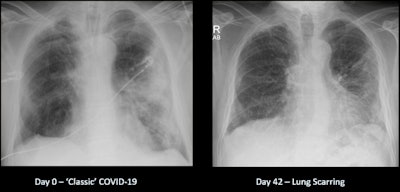

Lung fibrosis after COVID-19 can be particularly worrisome, and he indicated that "even if there's 20% to 30% of cases that result in potential lung scarring, 20% to 30% of half a million people is a far bigger number and a far bigger resource burden on the health service than 20% to 30% of 10,000 patients."

A significant proportion of patients do get some significant lung scarring, and many hospitals are organizing post-COVID-19 meetings to specifically follow up these patients.

"The lungs take a long time to recover in those patients, which is not the case for a chest infection," he continued. "Usually, chest infections have cleared by six weeks at the latest, whereas we're seeing COVID patients six months on who still have some mild lung damage; they feel short of breath when they're doing even mild activity like going for a walk."

The lung scarring/fibrosis leads to a distortion of the lung, preventing effective oxygenation of the blood to those areas of damage and resulting in fatigue and lethargy and an inability to exercise. "Patients may be tired for a particularly long time, and the concerning thing is lung scarring is irreversible, so patients may have that for the rest of their lives."